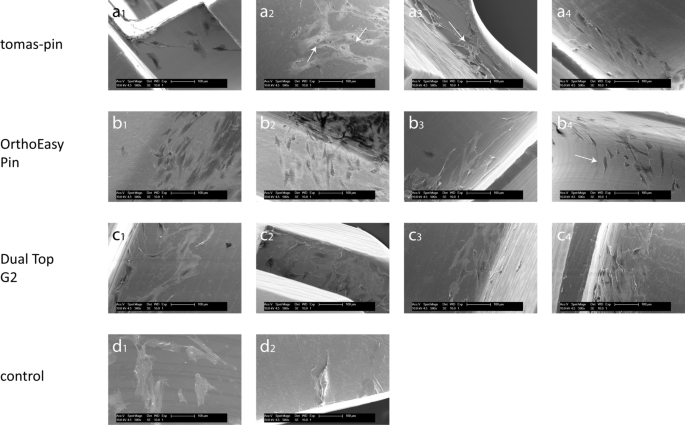

For the qualitative assessment of cell adhesion to the screws, scanning electron micrographs were taken (Figs. 4, 5). Fibroblasts and osteoblasts adhered to all sections of all OMIs. No sections were detected without cells attached.

Fibroblast adhesion to miniscrews and controls. Scanning electron micrograph of fibroblast adhesion to screws and controls at 500× magnification. tomas-pin—(a1) Head: spindle-shaped cells. (a2) Neck: moderately elongated cells with polygonal shape. (a3) Thread: spindle-shaped cells oriented along the grooves. (a4) Thread (apex): spindle-shaped cells aligned along the grooves and with numerous protrusions (arrow). OrthoEasy Pin—(b1) Head: polygonal and spindle-shaped cells. (b2) Neck: moderately elongated cells with polygonal shape. (b3) Thread: spindle-shaped cells. (b4) Thread: spindle-shaped cells, the alignment along the grooves is particularly evident at the edge of the indentations (arrow). Dual Top G2—(c1) Head: spindle-shaped cells with orientation along the grooves. (c2) Head: polygonal and spindle-shaped cells. (c3) Neck: moderately elongated cells with polygonal shape. (c4) Thread: spindle-shaped cells with orientation along the grooves. control sample—(d1) TC coverslips (positive control): polygonal and spindle-shaped cells with numerous protrusions. (d2) PTFE (negative control): moderately elongated and spherical cells.

TC coverslips were used as a positive control to illustrate the cell shape under optimal adhesion conditions. The cell density was high on these coverslips; fibroblasts were elongated and spindle-shaped, while osteoblasts were flat and polygonal shaped. PTFE was used as a negative control to observe the cell shape under poor adhesion conditions. Very few cells adhered to PTFE, and were either rounded or with very limited spreading.

Similar to the positive control conditions, fibroblasts were predominantly spindle-shaped and osteoblasts were predominantly polygonal shaped when adhered to the miniscrews. However, the shape of the cells was affected by the implant surface. In grooved areas (such as on the screw thread), both cell types were more spread out and spindle-shaped and orientated themselves parallel to the grooves. On smooth surfaces (such as the implant neck), osteoblasts were predominantly polygonal shaped and fibroblasts were only moderately spread out; spreading was more pronounced on the thread. The cells generally attached to the screw surface and extended numerous protrusions.

No differences in cell adhesion were detected between the different miniscrews. The OrthoEasy Pin was the only screw with an oxide layer, but this did not seem to affect cell adhesion to the implant surface. Isolated spherical-shaped osteoblasts and fibroblasts were observed on all miniscrews. Overall, cell density appeared higher on grooved surfaces than on smooth surfaces. However, cell density could not be quantified from SEM images.